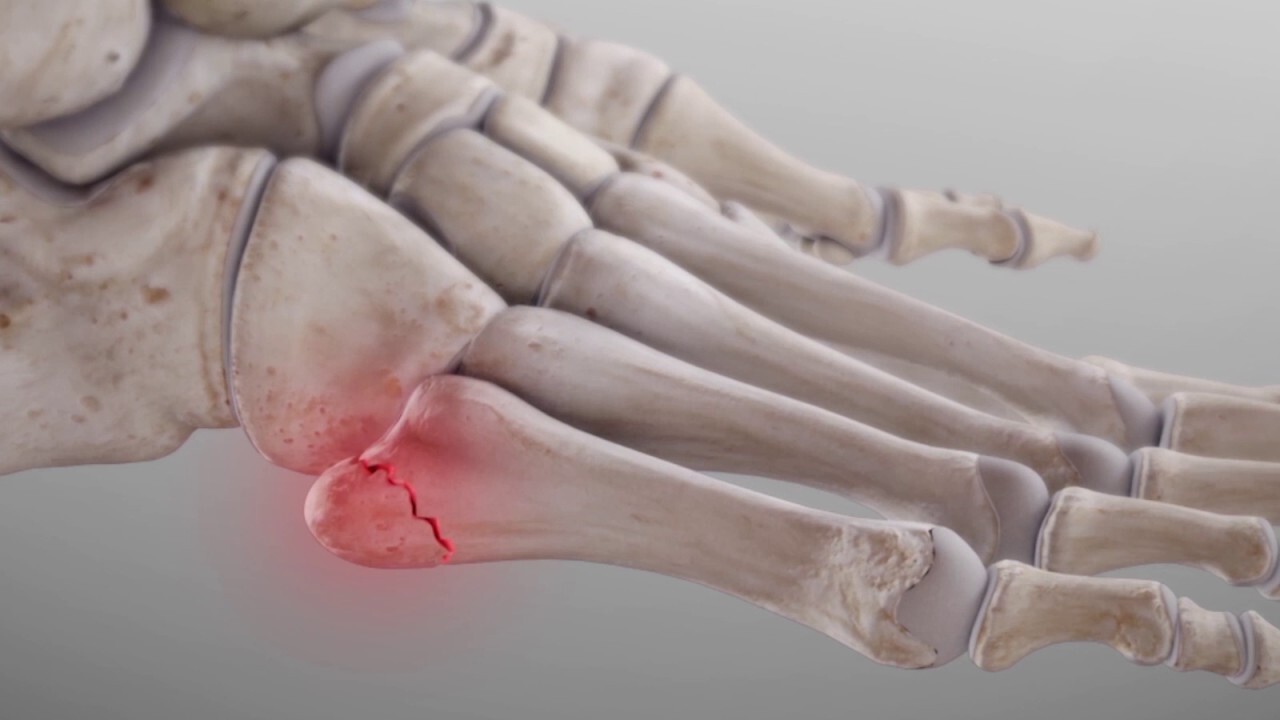

발가락 골절의 치료 방법

- 깁스 치료: 뼈가 크게 부러진 경우에는 깁스로 고정하는 방법이 일반적입니다.

- 스플린트: 뼈에 금만 간 경우, 즉 미세한 골절의 경우에는 발가락용 스플린트로 치료가 가능합니다.

- 수술: 복합 골절이나 압박 골절의 경우에는 핀을 박는 수술이 필요할 수 있습니다.

- 금속판 사용: 뼈가 조각나거나 비스듬하게 부러진 경우에는 금속판을 덧대어 고정하기도 합니다.